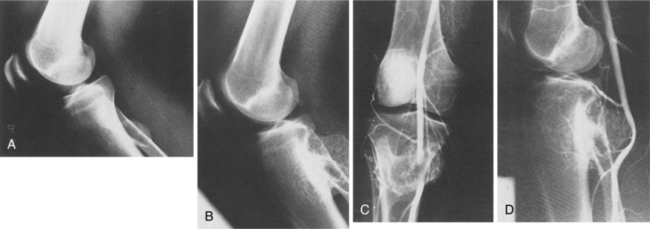

The tumor is soft, sometimes viscous, with hemorrhagic necrosis caused by the rapid tumor growth outpacing its blood supply. The cortical bone is affected through the haversian canals. The medullary cavity is affected, and infiltration of the bone marrow can progress extensively without radiographic evidence of bone destruction. When the tumor perforates the cortex of the bone shaft and elevates the periosteum, the consequent reactive bone formation causes layered calcification referred to as an “onion-skin” appearance seen radiographically (Fig. 26-14).

Figure 26-14 Ewing’s sarcoma of the humerus. Bone destruction is seen in the proximal metadiaphysis. The cortex is infiltrated and a multilaminar periosteal reaction with an onion-skin appearance is present medially; Codman’s triangles are present on the lateral aspect. (From Grainger RG, Allison D: Grainger and Allison’s diagnostic radiology: a textbook of medical imaging, ed 4, Philadelphia, 2001, Churchill Livingstone.)

Anyone suspected of having Ewing’s sarcoma is staged for both local and metastatic disease. Radiographs show an obvious lytic process with a moth-eaten appearance involving a diffuse area of bone (Fig. 26-15). As mentioned, an onion-skin formation may be seen, which is due to layers of reactive bone (see Fig. 26-14). On radiographs the appearance may not differentiate this lesion from osteomyelitis or osteosarcoma.

Figure 26-15 Ewing’s sarcoma. A, A mixed lytic-sclerotic lesion in the femur of a child with periostitis that is amorphous and sunburst that is characteristic of Ewing’s sarcoma. B, This is a predominantly sclerotic process with large amounts of sunburst periostitis in the diaphysis of a femur that, on biopsy, was found to be Ewing’s sarcoma. (From Helms C: Fundamentals of skeletal radiology: benign cystic lesions, Philadelphia, 1989, WB Saunders.)